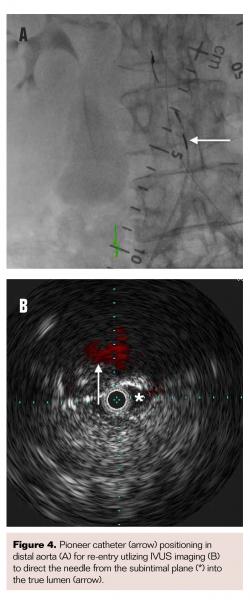

An Ocelot catheter (Avinger) was advanced from the right CFA to cross the chronic total occlusion (CTO) in the CIA (Figure 3A) with optical coherence tomography (OCT) imaging (Figure 3B) to allow direct visualization during crossing and to maintain intraluminal position. Although the catheter maintained this position up to the aortoiliac bifurcation, it entered into a subintimal plane in the distal aorta due to heavy distal calcifications despite multiple attempts to maneuver the catheter within the lumen. A Grand Slam guidewire (Abbott Vascular) was maintained in this position in the subintimal plane from the right femoral access. The same steps were then performed from the left CFA to wire the subintimal plane in the distal aorta and another Grand Slam guidewire maintained in this position from the left femoral access. A Pioneer Plus re-entry catheter (Volcano Corporation) was then advanced over the Grand Slam wire from the right-sided access (Figure 4A) to re-enter the true lumen of the aorta with intravascular ultrasound (IVUS) guidance (Figure 4B), allowing the re-entry wire to advance into the proximal descending aorta. The same technique was then repeated from the left-sided access to maintain a guidewire in the proximal descending aorta. Simultaneous balloon angioplasty was performed of the reentry site with two 6 x 40 mm Sterling balloons (Boston Scientific). A single iCAST 10 mm x 38 mm balloon-expandable covered stent (Maquet) was deployed as a distal aortic cuff in the infrarenal position (Figure 5A). Two iCAST 7 mm x 59 mm covered stents were then simultaneously deployed to extend from within the initial aortic cuff stent into the bilateral CIAs (Figure 5B). Two additional iCAST 7 mm x 59 mm stents were then deployed in bilateral CIAs to cover the entire occluded segment. Final aortogram from the left radial artery access site confirmed patent aortic stents with bilateral limb extensions with brisk flow (Figure 6). Both internal iliac arteries were noted to be patent. Hemostasis was achieved in bilateral femoral access sites via manual compression upon normalization of activated clotting time.